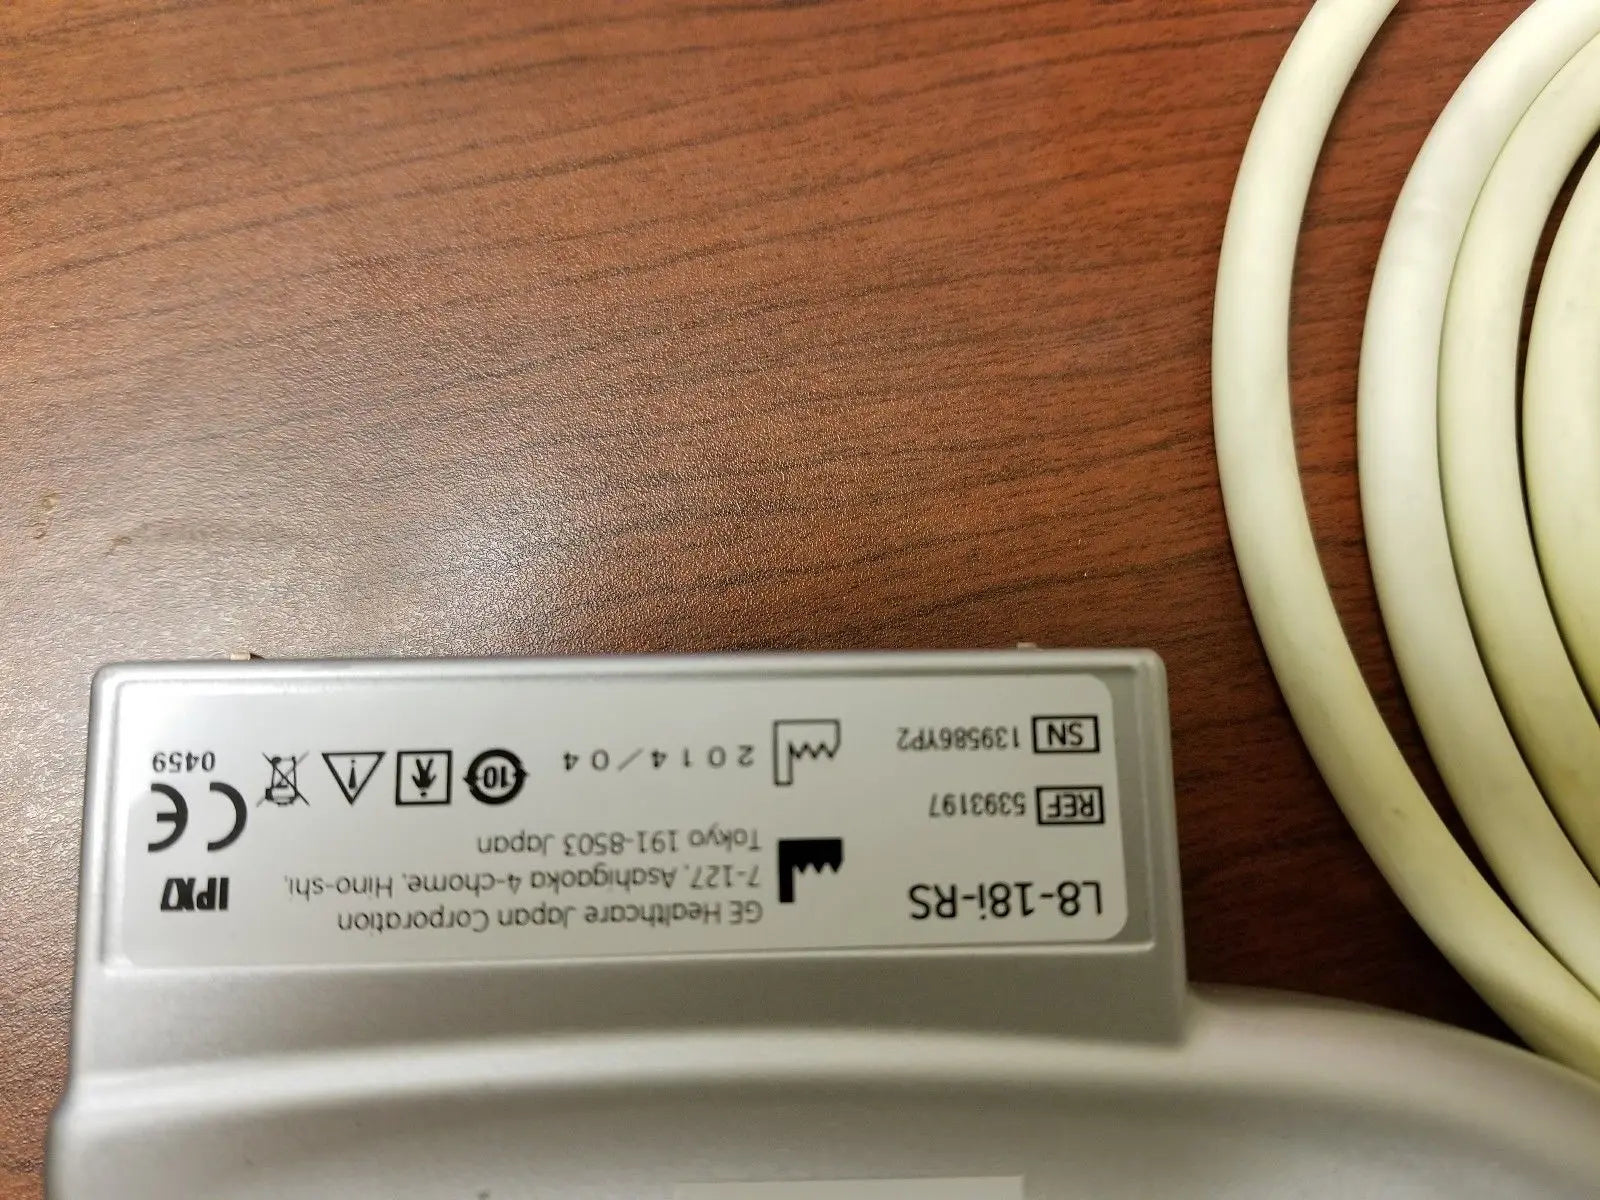

DIAGNOSTIC ULTRASOUND MACHINES FOR SALE

2014 GE L8-18i -RS probe for GE Ultrasound

Sale price$ 7,170.06